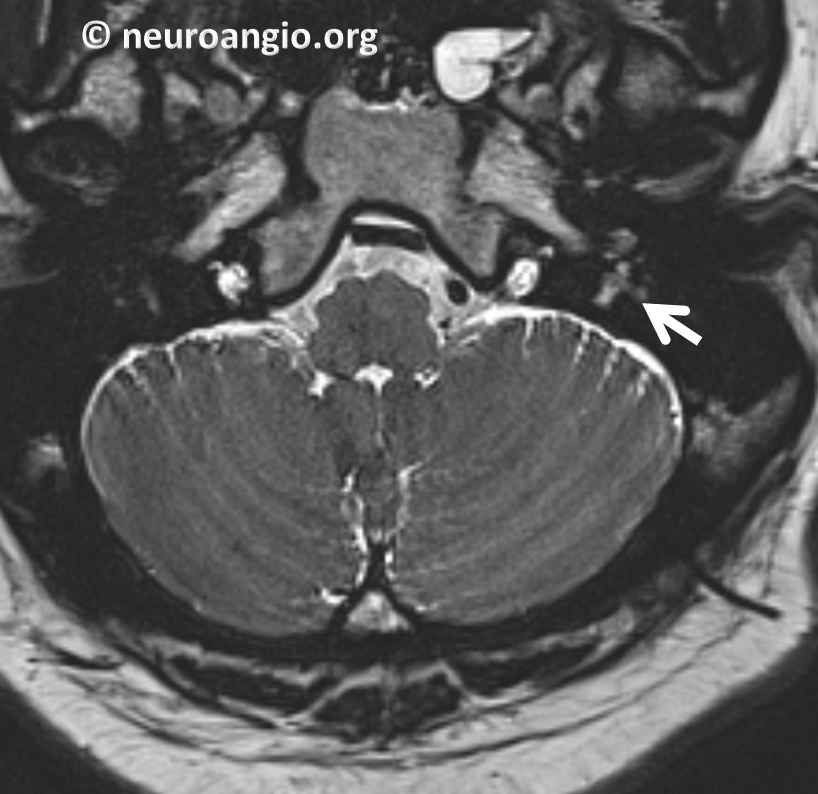

From neuroangio.org

Pulsatile Tinnitus Glomus Tympanicum Tinnitus Brain Tumor There are just a few millimeters of space between the brain and the skull. Tinnitus is a very common symptom of acoustic neuromas and many other inner ear conditions. But a benign tumour can. It is described as a benign tumour because it cannot spread into the brain. Why might a brain tumor cause tinnitus and dizziness? Tinnitus — or. Tinnitus Brain Tumor.